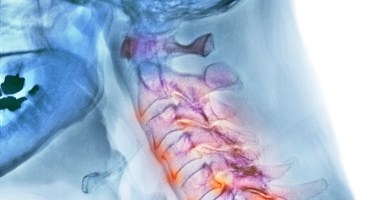

Latigazo Cervical: Anatomía y hallazgos en Radiodiagnóstico